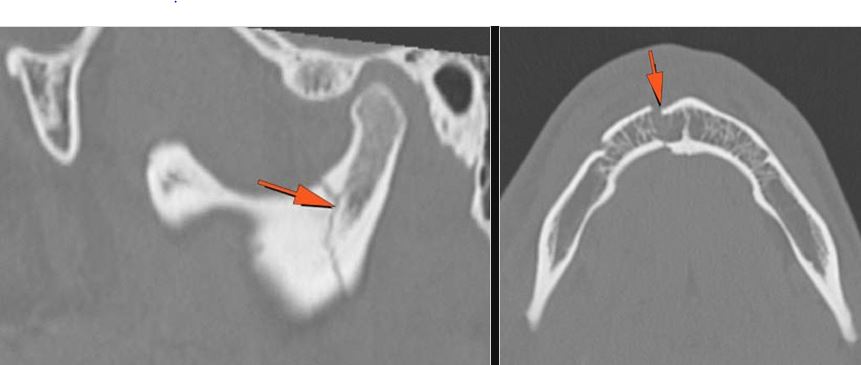

The medial, lateral and posterior maxillary walls are fractured. |

Yes | NA |

The infraorbital rims and orbital process of the zygoma and/or frontozygomatic suture are fractured. |

The alveolar ridge, premaxilla, and/or the palatine process of the maxillary bones on either side are fractured. |

The pterygoid processes of the sphenoid bone are fractured. |

The mesial naso-orbito-ethmoid complex is fractured. Specifically, there is bony injury of the nasal bones or the frontal process of the maxilla and the medial walls of the orbit are abnormal. |

The frontal bone and frontal sinus inner and outer tables are fractured. |

LeFort type III, orbital zygomatic and orbital floor and fronto - naso-ethmoidal complex fractures with possible injury optic nerve/sheath - extent described above.